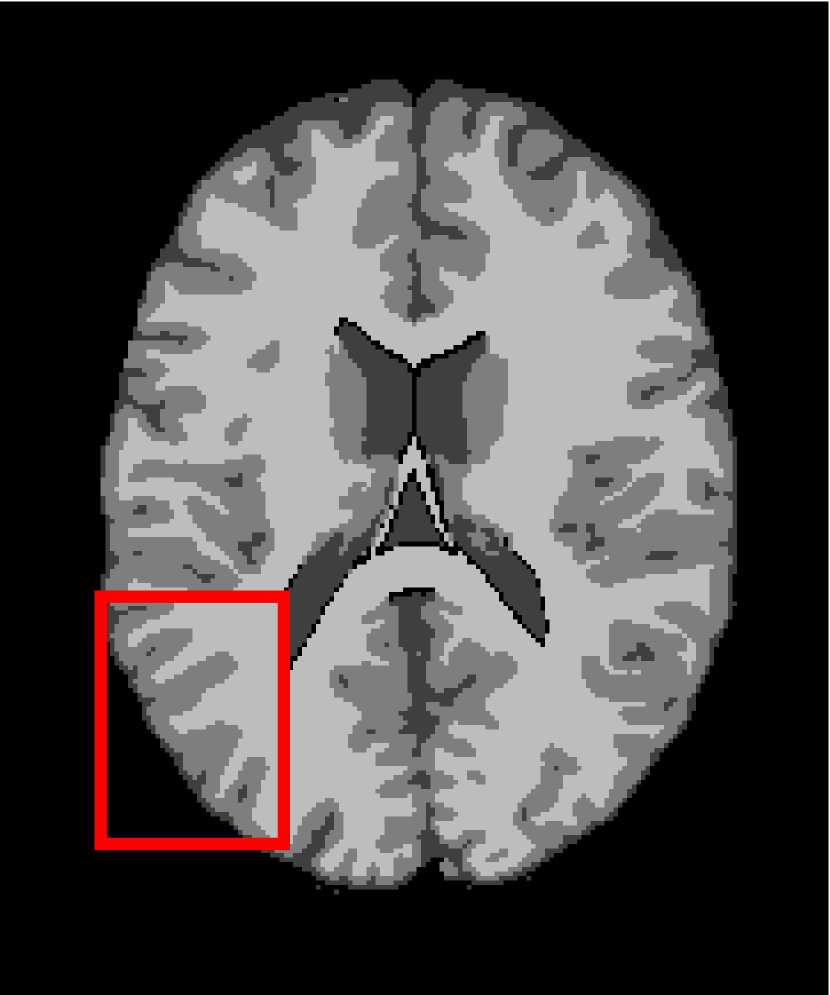

4.4.2 Results on Medical Images

Next, we representatively segment five medical images from BrianWeb. They are represented as five slices in the axial plane with a sequence of 70, 80, 90, 100 and 110, which are generated by T1 modality with slice thickness of 1mm resolution, 9% noise and 20% intensity non-uniformity. Here, we set c=4𝑐4c=4 for all cases. The comparison between WRFCM and its peers are shown in Fig. 9 and Table II. The best values are in bold.

Figure 9: Segmentation results on five medical images. The parameter: ϕ=5.35italic-ϕ5.35\phi=5.35. From top to bottom: noisy images, ground truth, and results of FCM_S1, FCM_S2, FLICM, KWFLICM, FRFCM, WFCM, DSFCM_N, and WRFCM.

TABLE II: Segmentation performance (%) on medical images in BrianWeb

Algorithm Fig. 9 column 1 Fig. 9 column 2 Fig. 9 column 3 Fig. 9 column 4 Fig. 9 column 5

SA SDS MCC SA SDS MCC SA SDS MCC SA SDS MCC SA SDS MCC

FCM_S1 75.756 97.852 96.225 75.026 98.109 96.656 79.792 98.452 97.334 81.887 98.614 97.680 81.869 94.254 90.947

FCM_S2 75.769 98.119 96.664 74.970 98.176 96.765 79.886 98.458 97.338 82.073 98.625 97.695 81.788 98.223 97.195

FLICM 74.998 98.070 96.568 74.185 98.122 96.660 79.099 98.515 97.432 81.447 98.627 97.691 81.668 98.273 97.260

KWFLICM 74.840 98.259 96.878 73.839 97.860 96.190 79.560 98.453 97.316 81.887 98.482 97.443 81.370 98.297 97.286

FRFCM 75.853 97.620 95.775 75.514 97.660 95.830 80.283 98.278 97.013 81.852 98.319 97.171 81.666 98.079 96.945

WFCM 75.507 97.124 94.957 74.471 97.213 95.045 79.316 97.845 96.283 81.358 97.546 95.211 81.452 95.247 92.501

DSFCM_N 76.400 92.325 86.262 75.288 91.574 85.095 79.861 97.678 95.996 81.831 93.304 88.829 81.750 94.302 91.024

WRFCM 82.317 98.966 98.147 82.141 98.298 96.970 83.914 98.963 98.202 83.533 99.170 98.603 84.615 98.429 97.511

By a view of the marked red square in Fig. 9, we find that FCM_S1, FCM_S2, FLICM, KWFLICM and DSFCM_N are vulnerable to noise and intensity non-uniformity. They give rise to the change of topological shapes to some extent. Unlike them, FRFCM and WFCM achieve sufficient noise removal. However, they produce overly smooth contours. Compared with its seven peers, WRFCM can not only suppress noise adequately but also acquire accurate contours. Moreover, it yields the visual result closer to ground truth than its peers. As Table II shows, WRFCM obtains optimal SA, SDS and MCC results for all five medical images. As a conclusion, it outperforms its peers visually and quantitatively.